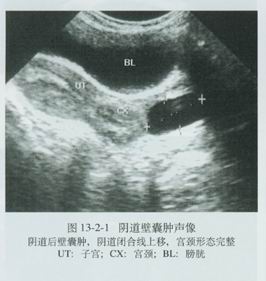

①陰道囊腫:陰道囊腫又分為上皮包含囊腫和胚胎遺留性囊腫兩類。上皮包含囊腫是由於分娩時陰道黏膜受損,或陰道手術縫合時陰道黏膜被捲入陰道深層,傷口癒合後此黏膜繼續增生脫屑,然後液化形成囊腫。一般無症狀,常於檢查時發現。胚胎遺留性囊腫又稱中腎管囊腫,陰道旁的中腎管如有阻塞,分泌物瀦留可形成囊腫,在陰道側壁或下段的前壁可見到,呈成串或多發,如葡萄或桌球大小,囊腫壁薄為單房。一般沒有症狀不需治療,如較大或發生感染可行剔除術。